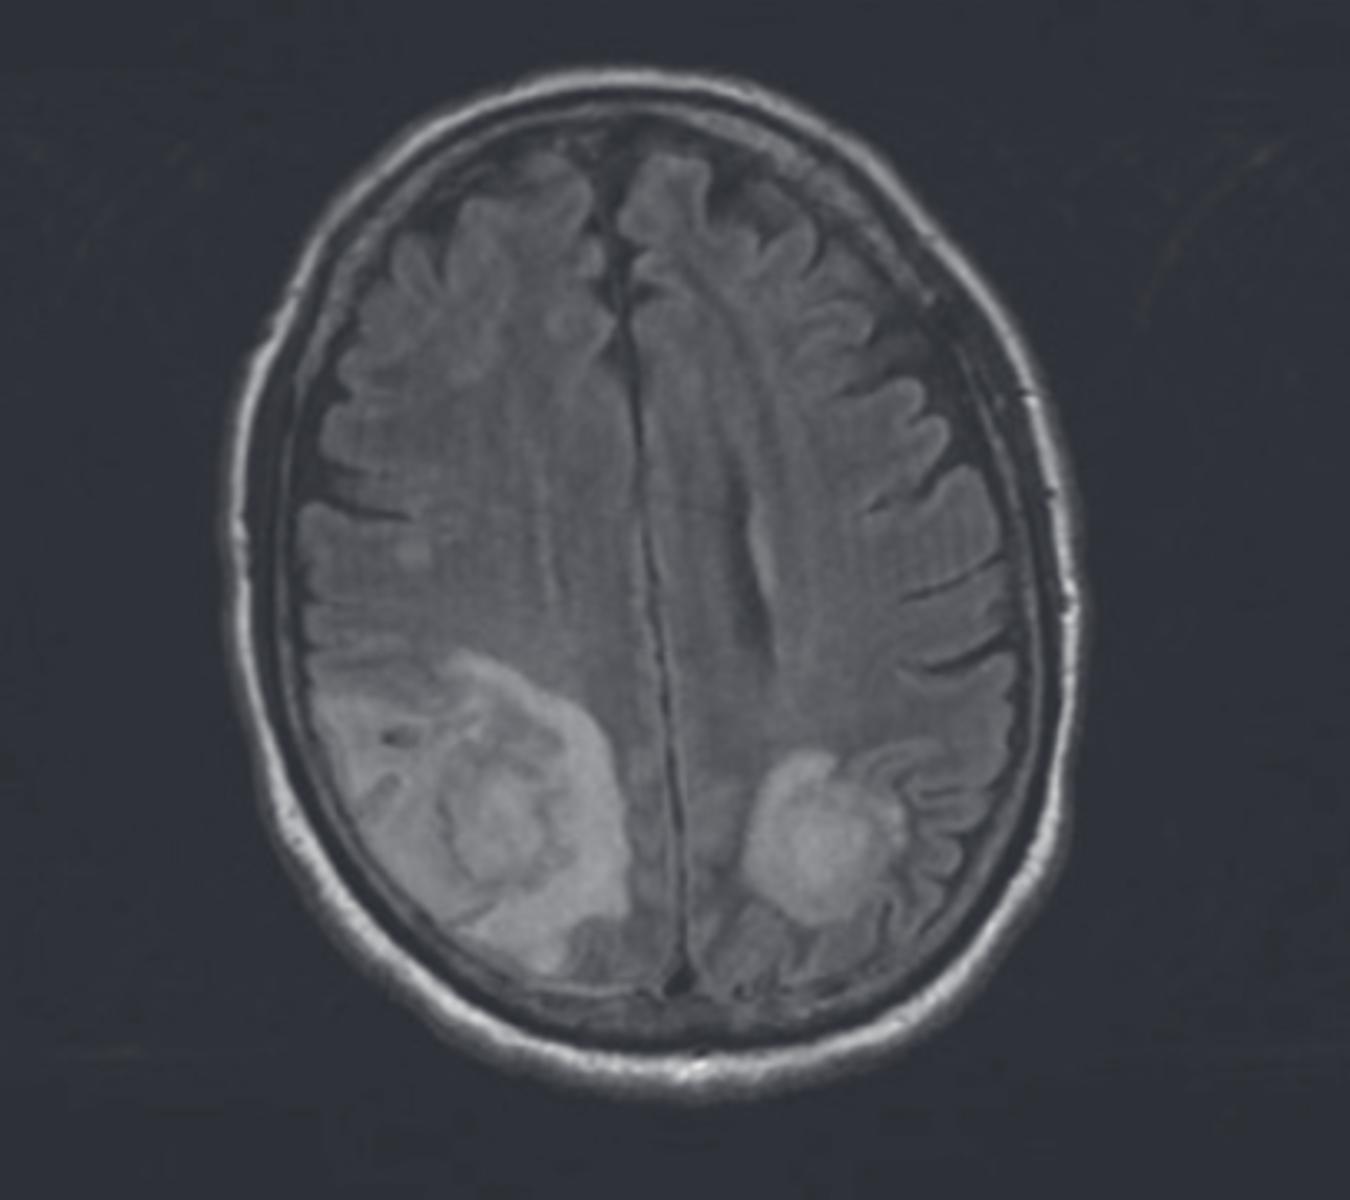

Ibrutinib-associated aspergillosis

• Retrospective French surveillance study identified 33 cases of aspergillosis in ibrutinib-treated patients with CLL

• CNS aspergillosis in 11/27 (40%), most cases within 3 months of starting therapy

• All patients had refractory/relapsed CLL and other predisposing risk factors